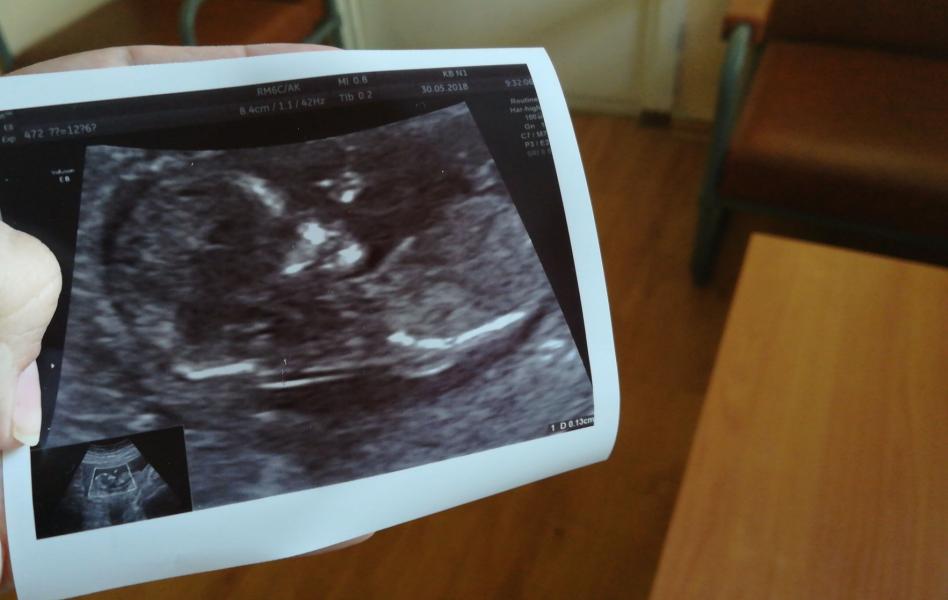

Первый скрининг пройден😍

Кровь ещё готовится, а вот по узи все отлично❤️сердечко 160, ручки, ножки, все на месте, показала желудок, мочевой, череп посмотрели, на фото успел помахать своей лапкой мой сладкий малыш❤️❤️❤️когда зашла в кабинет попросила если увидит пол не говорить мне а написать на бумажке, она сказала, что все увидела, но пока не будет говорить 😄но когда Варя подошла к экрану и сказала "мааааам, это мой братик, это Лёня!!!" врач сказала, что Варя уже все знает 😄😄поэтому подозрения есть...